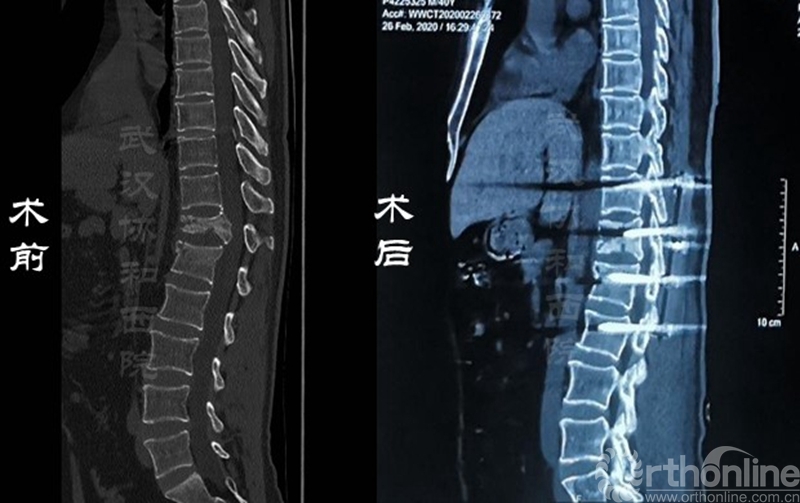

影像学资料对比

郜勇:该患者已于3月11日治愈出院,从目前情况来看,患者术后各项机能恢复地比较理想。首先,患者已连续多日无发热症状,CT显示新冠肺炎的磨玻璃改变已经吸收,核酸检测已经连续两次呈阴性,完全达到了新冠肺炎第七版诊疗方案的出院标准。

其次,患者的脊柱骨折、截瘫和双下肢疼痛的症状明显好转,双下肢感觉功能基本恢复,双侧髋关节、膝关节和踝关节肌力从术前的不到2级恢复到4级,目前患者在助步器辅助下已经逐步开始行走,整体治疗效果达到了预期。

此次手术的新冠肺炎患者肺部症状比较轻微,CT显示肺部磨玻璃病变范围不大,但是患者的胸腰椎压缩性骨折很严重,双下肢肌力均不到2级,感觉严重减退,大小便失禁,需要进行抢救性手术治疗。